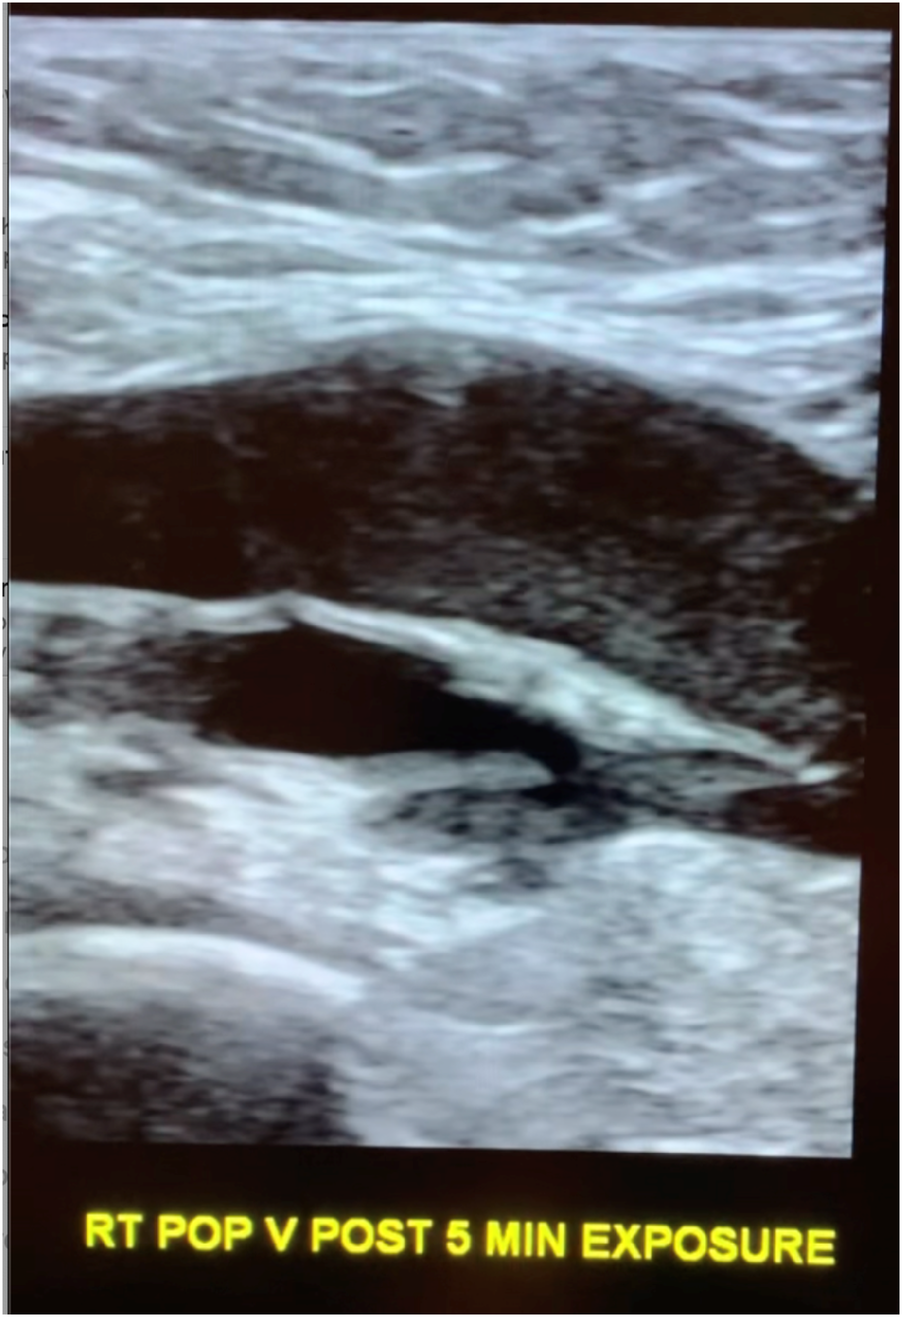

Figure 2

Longitudinal popliteal vein after 5 min of exposure demonstrating rouleaux.

Following exposure, the subject's popliteal vein was reimaged (Figure 2). No changes were made in between the two scans on the ultrasound consol. Specifically, there was no adjustment to the total gain or TGCs that could cause a change in apparent echogenicity of the popliteal structures as compared to pre-exposure images. A post exposure cine loop demonstrates abnormal heterogeneous, predominately hypoechoic material sluggishly moving to and fro within the popliteal vein and nearby tributaries. The sonographic appearance is typical for rouleaux formation, named for the histologic appearance of red blood cells when they are stacked upon one another, resembling a stack of coins. The subject experienced no symptoms.